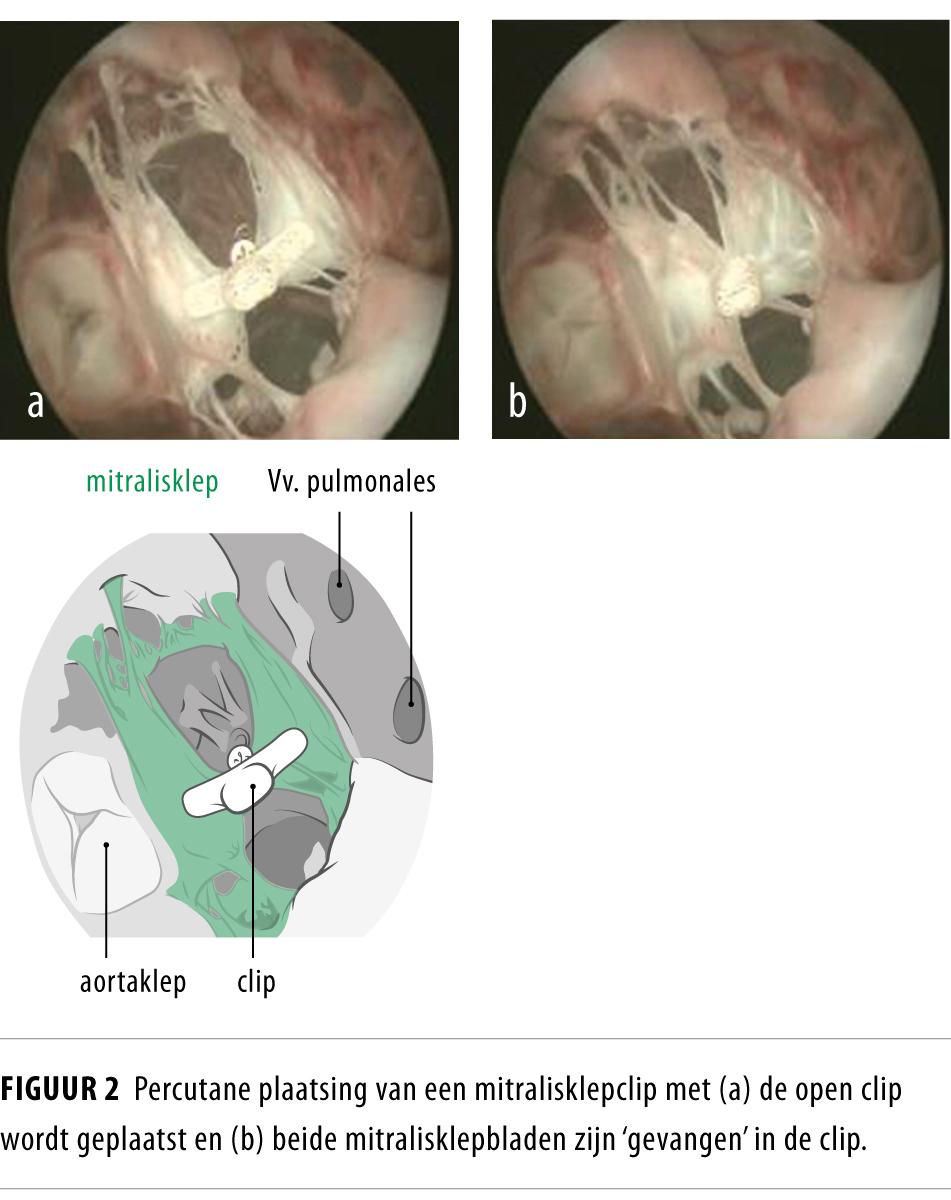

• Percutane klepimplantaties of technieken om kleplekkages te verhelpen hebben de prognose van inoperabele patiënten verbeterd.